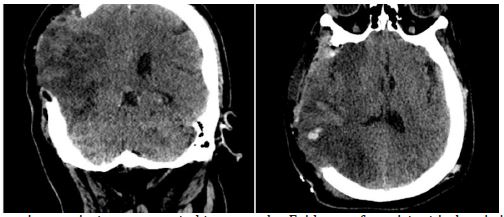

Upon discharge, the patient had an ECG score of 15, a Karnofsky Performance Score of 70, and residual hemiparesis of 3/5. At a three-month follow-up, he had improved to a Karnofsky score of 90 and 4/5 strength in the left upper limb, with persistent left facial nerve palsy (Figure 5).